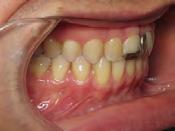

Approximately six months after insertion of the RPE, digital scans were taken for SureSmile custom wires and the patient was scheduled for the SFOT procedure with the oral surgeon. The RPE was removed, SureSmile wires inserted and segmental corticotomies performed, immediately followed by further vertical elastics on the right side (Figure

4). Archwires were upgraded incrementally into 19 x 25 SS. Once the bite was completely closed, the patient was referred to the myofunctional therapist to begin treatment. Eight sessions of myofunctional exercises were performed, focusing on muscle building, toning, synchronicity and awareness. Improvement in correct chewing, swallowing and resting postures of the lip and tongue were addressed. All appliances were removed 21 months after initial insertion (Figure 5), and the patient was referred to a re-

Figure 4. Post-corticotomy, with SureSmile custom wires.